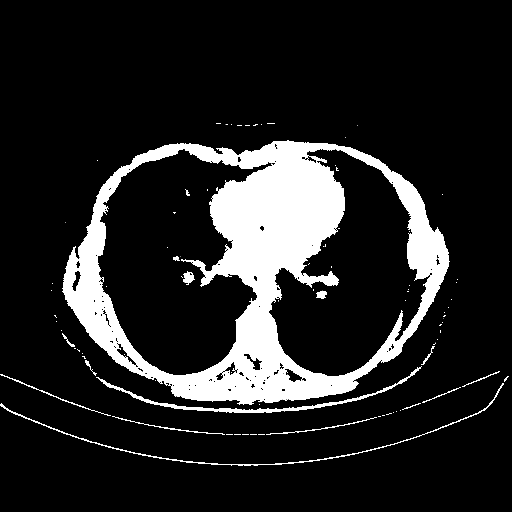

Generated VENOUS CT scan (A→B translation)

Full window (WL 1023.5, WW 4095 β†’ Low βˆ’1024, High +3071)

Actual HU range: [-1024.0, 3071.0]